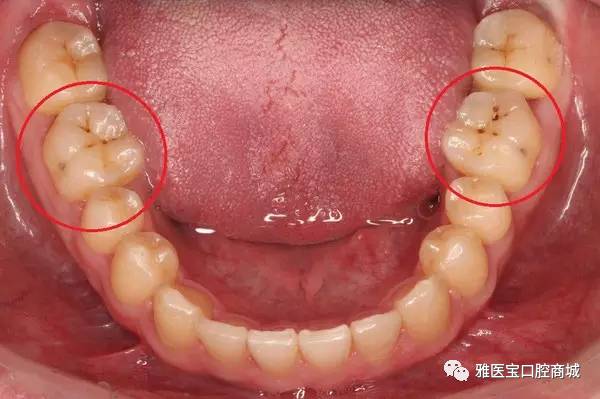

3、色素沉着与龋齿:长期食用含有色素的食品或饮料,如咖啡、茶、红酒等,可能会导致牙齿色素沉着,龋齿也可能导致牙齿变黑并产生疼痛。